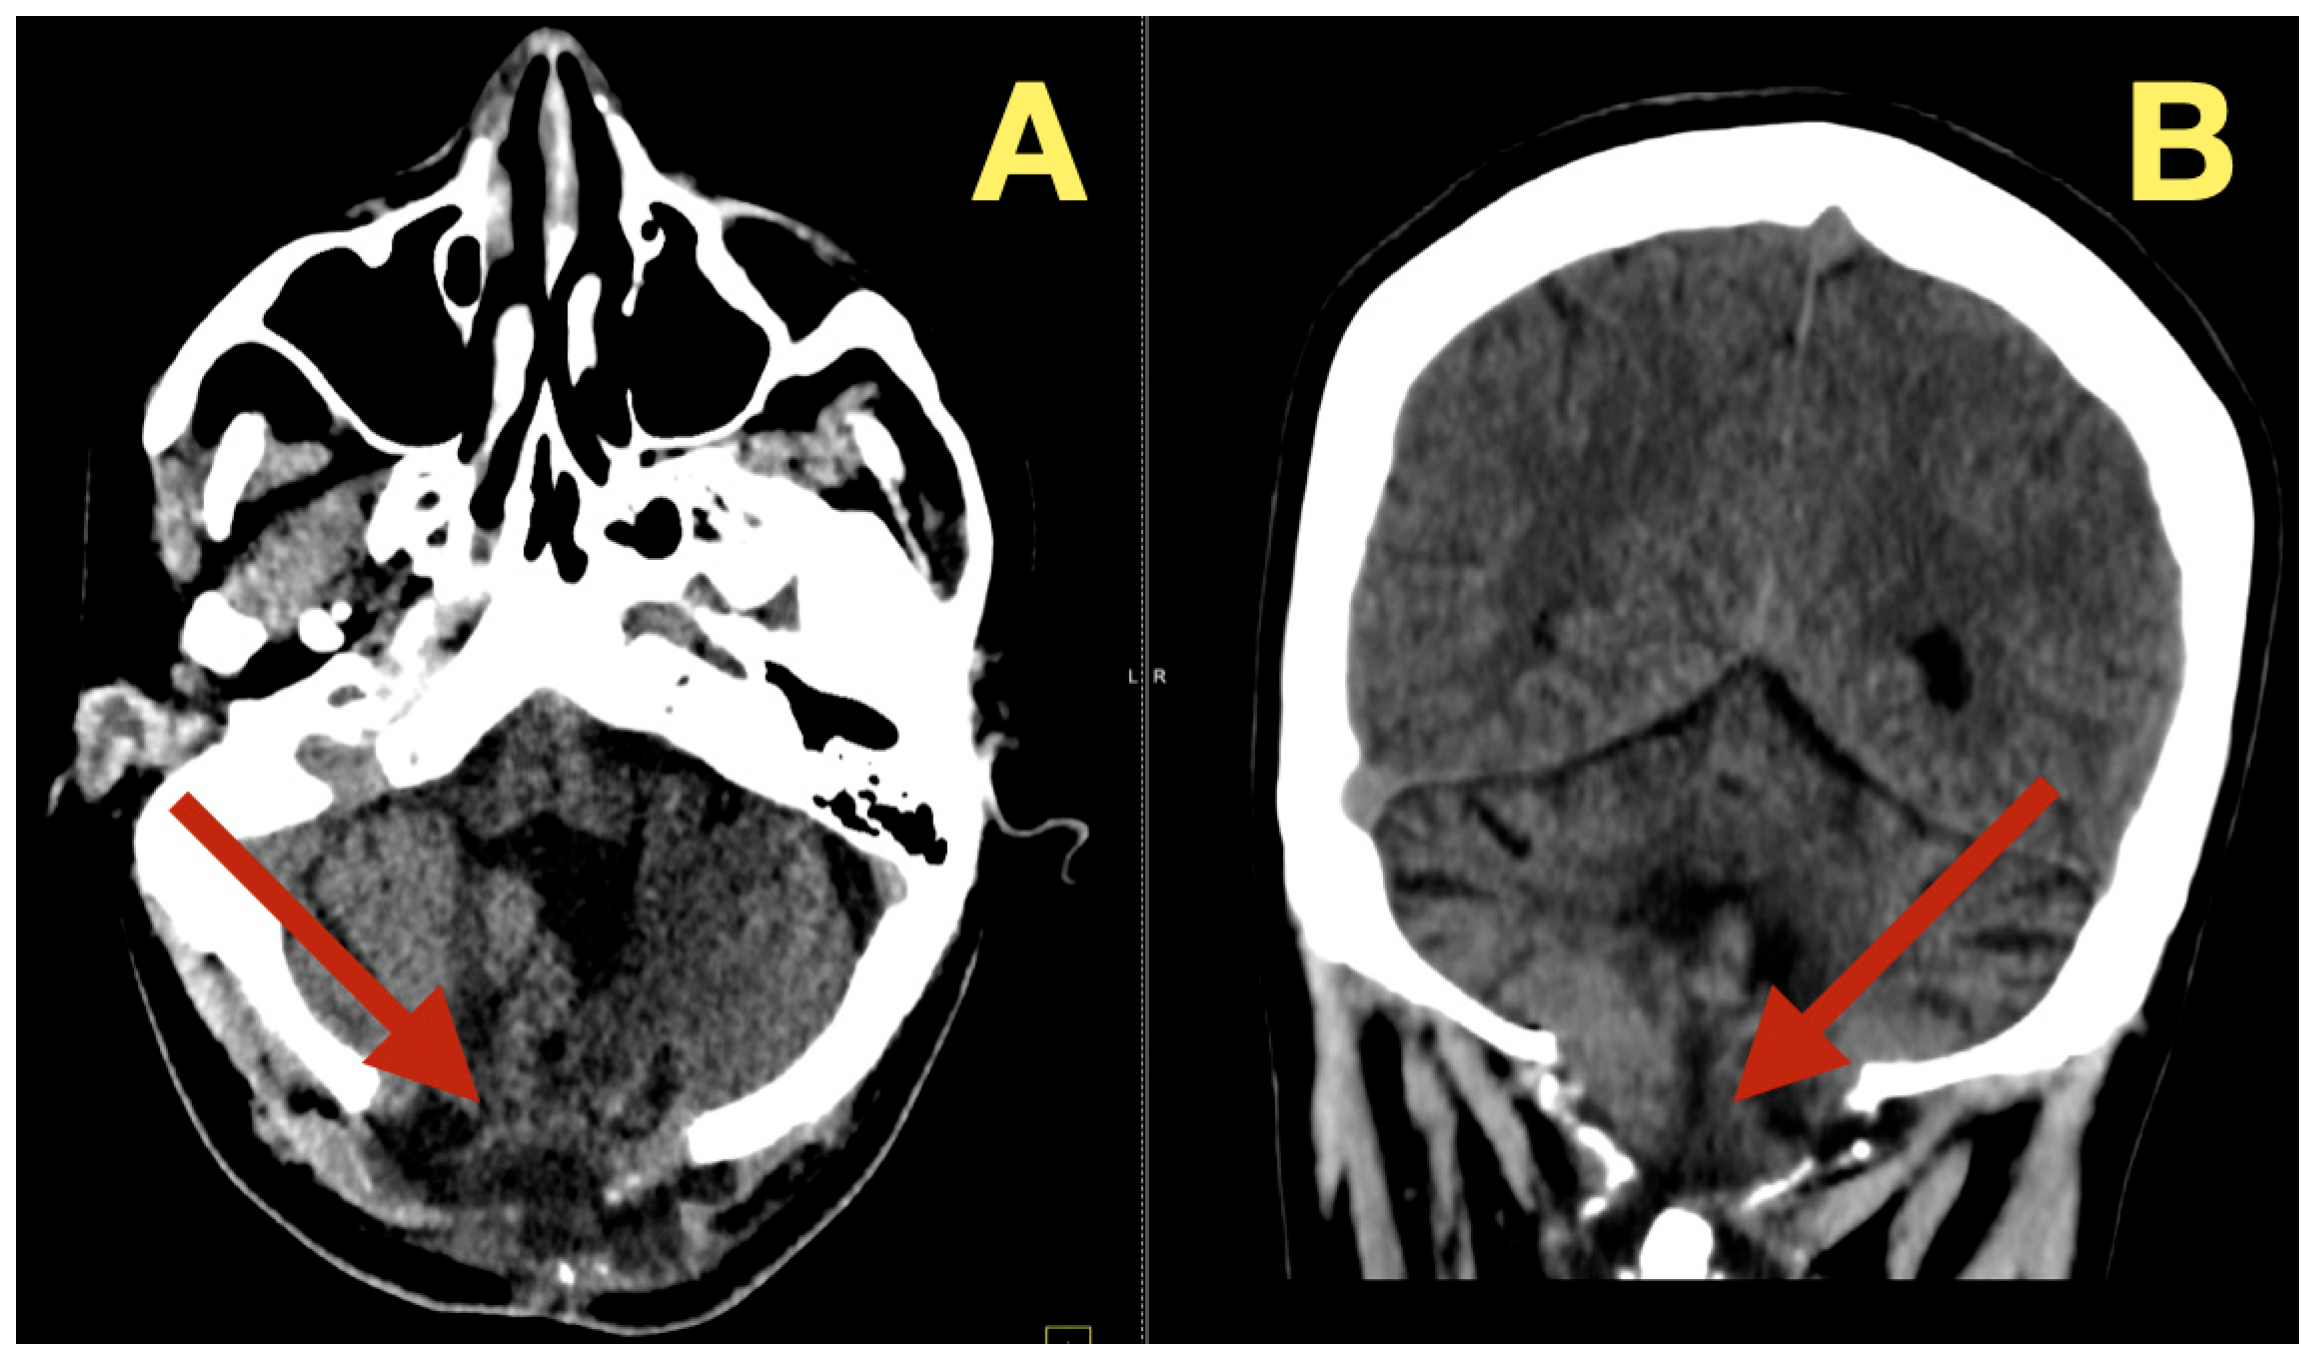

CT scans completed on the first post-operative day (Figure 3) were utilized to exclude hemorrhage and assess early ventricular diameter; they indicated posterior fossa re-expansion, full reopening of the fourth ventricle, normal brainstem convexity, and no early hydrocephalus. A second CT scan completed 7 days post-operatively (Figure 4) verified stable ventricular and outlet patency and excluded late onset hydrocephalus. The one month follow-up CT scan (Figure 5) provided a baseline for long-term comparisons. Later surveillance relied upon MRI including DWI to exclude diffusion-positive residual or recurrence.

Follow up CT scans three months after surgery (Figure 6), confirmed continued decompression of the fourth ventricle and structural stability, as evidenced by stable size of the fourth ventricle, open CSF pathways, and absence of inflammation or scarring. The patient was clinically normal and able to resume all normal activities

Figure 6. Three-month postoperative CT scan. (A): Axial CT revealing sustained decompression of the fourth ventricle and preservation of the posterior-fossa configuration (arrow). (B): Coronal CT showing symmetrical cerebellar folia and patent lateral recesses without evidence of recurrent mass (arrow). (C): Sagittal CT confirming persistent brainstem relaxation, patent foramen of Magendie, and absence of postoperative scarring (arrow).

Diagnostics 16 00129 g006